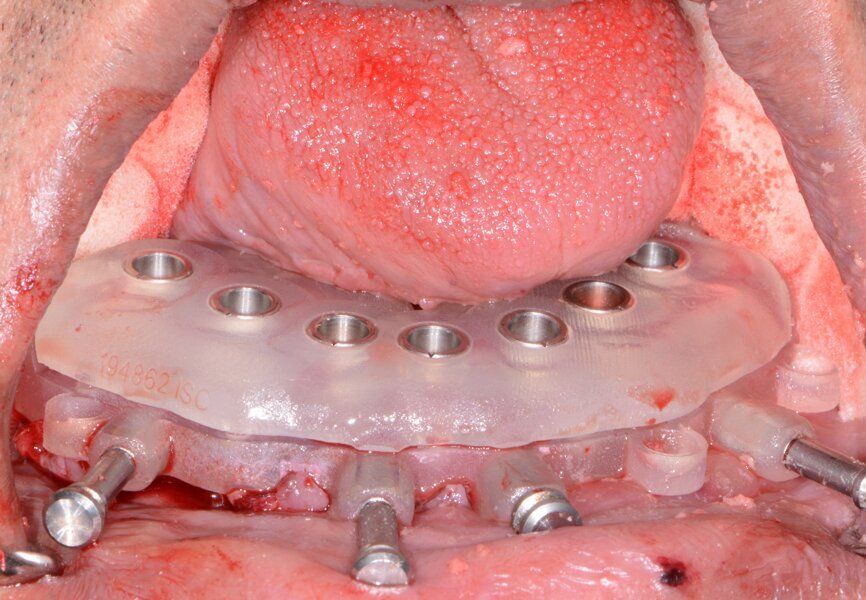

Fig. 10: Maxillary bone levelling guide.

Fig. 11: Maxillary implant surgical guide.

Once the virtual plan had been orchestrated and fully confirmed, the next appointment would be the planned surgery. The patient was appropriately sedated with intravenous medications, and local anaesthesia was administered in both arches. The maxillary teeth were atraumatically extracted utilising the Physics Forceps (GoldenDent). The tissue was then reflected using the Reflector instrument (GoldenDent) so that the bone levelling surgical guide (3DDX) would be fully seated and fixed with its respective retention pins (Fig. 10).

Once the appropriate bone levelling had been accomplished with the surgical handpiece, the universal implant surgical guide was positioned into the bone levelling guide and the sites for the implants were initiated with a designated 1.8 mm pilot drill in its appropriate key from the OCO Biomedical Guided Surgical System Kit (Fig. 11), utilising the Mont Blanc surgical handpiece (Anthogyr) and AEU 7000 surgical motor (Aseptico) at a speed of 1,200 rpm with copious amounts of sterile saline. Sequential osteotomy formers and keys from the OCO Biomedical Guided Kit were then used to shape the final osteotomies. Once the osteotomies were complete, a rotary implant driver was used to place the dental implants until increased torque was necessary (Fig. 12). The ratchet wrench was then connected to the adapter and the implants torqued to final depths, reaching a torque level of about 40–50 Ncm.